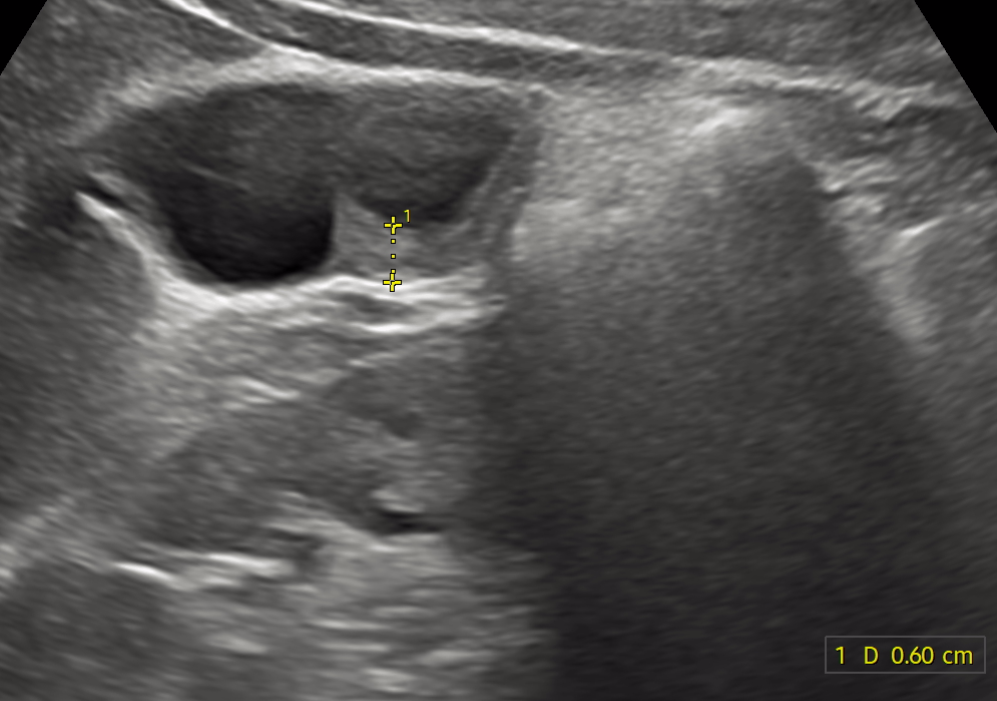

만 나이 25 남자입니다. 담낭암일 수 도 있나요? 가끔 과식할때 소화불량이 있어 우연치 않게 건강검진하다가 현재 초음파검사상 담낭벽비후 진단 받았고 ct결과 기다리는중입니다.

• 3번 째 사진

• 담낭벽의 비후 소견이 발견되었다면 담낭암에 의한 소견일 가능성이 존재합니다. 그렇지만 해당 소견이 무조건 암을 의미하는 것은 아니며 담낭의 염증 등 가능한 원인은 여러가지 있습니다.